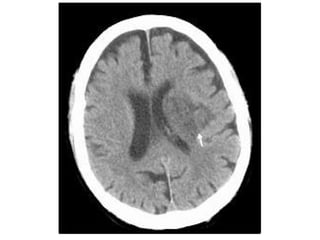

Acute Arterial Infarct - CT appearance

a) Low Density Region :

1-Loss of grey / white matter differentiation is a

feature of acute infarction and is the earliest

radiological abnormality (thought to be due to

decreased cerebral blood volume)

Normal GWM differentiation Loss of GWM differentiation